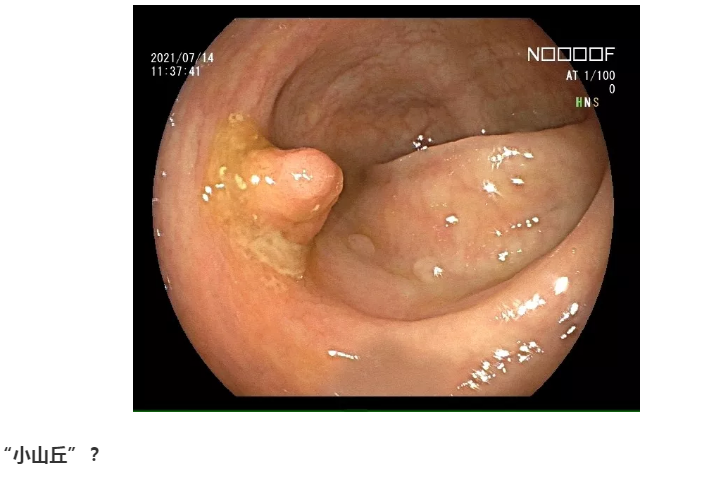

下面就是不一般的了,都是我的宝库,把库存翻出来亮亮相。大千世界,无奇不有。息肉经过进化变异,竟然也长成了各种各样的面孔,医生有时都差点认不出来。甚至都怀疑,你还是曾经的你吗?